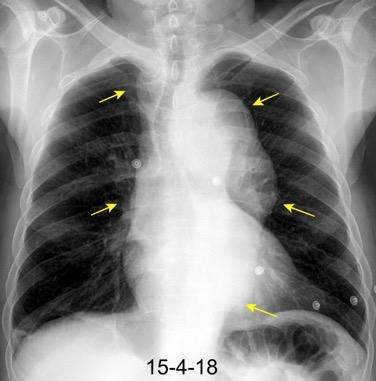

Triada de Garland

Ganglios paratraqueales derechos e hiliares bilaterales

95% de pacientes tienen ganglios hiliares bilaterales aislados o con afectación mediastínica (espec. paratraqueal derecho).

Criado E et al. Pulmonary sarcoidosis: typical and atypical manifestations at high-resolution CT with pathologic correlation. Radiographics. 2010